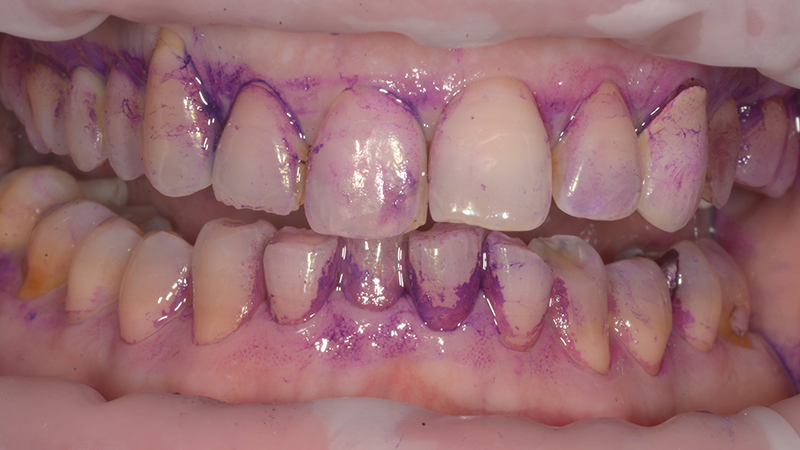

L’igienista dentale, in sinergia con tutto il team, ha il compito di costruire un’alleanza terapeutica efficace, informando il paziente e supportandolo nel controllo quotidiano dei fattori di rischio. Strumenti come la videocamera intraorale, i rivelatori di placca e la documentazione fotografica diventano alleati indispensabili per far “vedere” al paziente la malattia e aumentare la sua adesione alle istruzioni di igiene domiciliare. Le indicazioni devono essere

personalizzate in base alle caratteristiche individuali e verificate alla poltrona per garantirne l’efficacia.